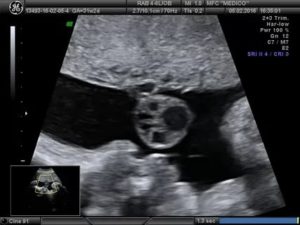

При этом, эхографически подобные аномалии являются анэхогенными образованиями, которые находятся в структуре пуповины, при этом, не нанося вреда ходу кровеносных сосудов.

- Истинные кисты пуповины. Они появляются из оставшихся частей аллантоисного протока (в некоторых случаях из остатков желточного). Во время проведения ультразвукового исследования, они имеют анэхогенное содержимое. При этом истинные образования могут иметь размер от полсантиметра и в некоторых случаях достигают размеров в 10 см. Зачастую они развиваются в непосредственной близости от самого тела плода. Однако проведение дифференцированного УЗИ является возможным не всегда.

При ультразвуковом обследовании кисты заметны. Они никак не влияют на кровообращение между плодом и плацентой.